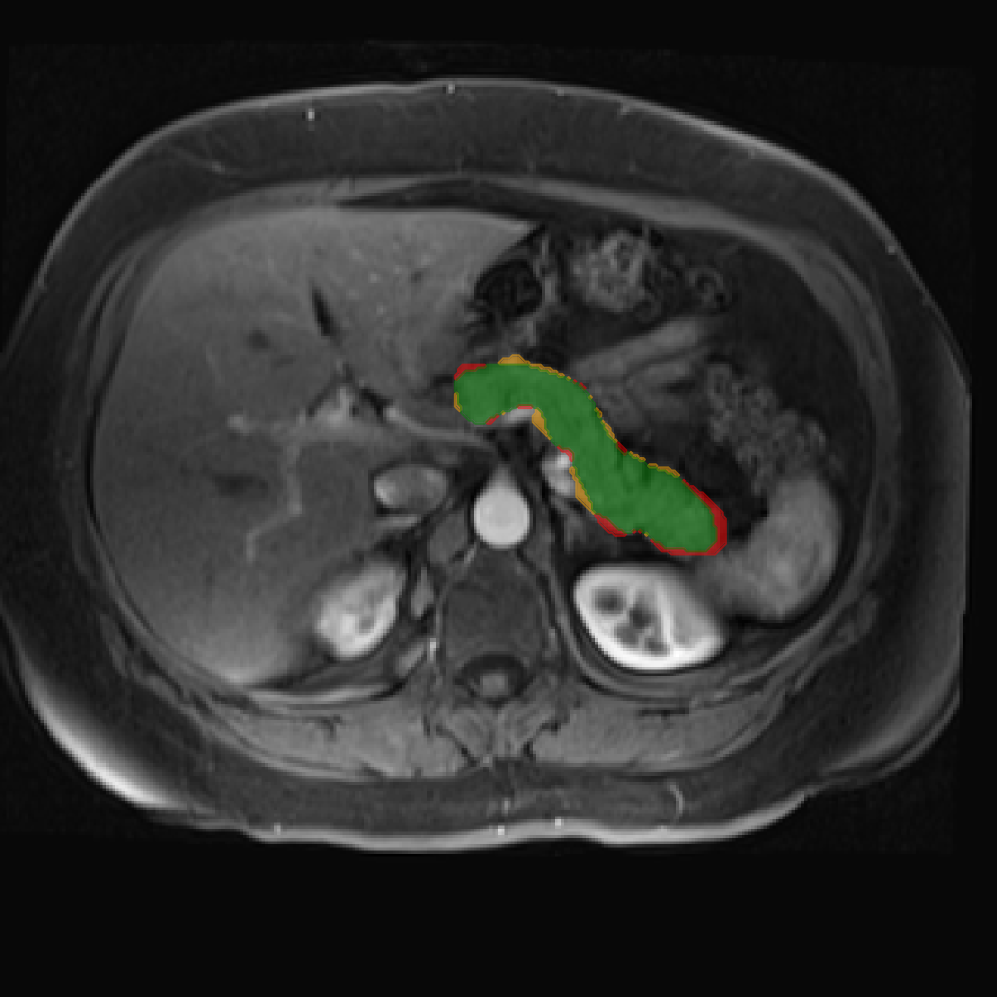

Accurate pancreas segmentation is a critical prerequisite for precise cyst analysis and classification. Recently, we developed PanSegNet [zhang2025large], a novel segmentation architecture incorporating linear self-attention layers [zhang2022dynamic] within the nnUNet framework [isensee2021nnu] to enhance global information modeling capabilities while maintaining computational efficiency (Fig. 1). PanSegNet demonstrated exceptional segmentation performance across both T1W and T2W modalities, achieving mean dice scores of 86.817.30% and 89.626.38%, respectively (Table 1, Fig. 2b-c). This performance significantly exceeded that of Swin-UNETR [hatamizadeh2021swin], one of the most used state-of-the-art transformer-based medical segmentation models, which achieved dice scores of 79.091.40% and 76.290.66% for T1W and T2W, respectively (). In this study, we integrated PanSegNet into our Cyst-X engine along with a classifier for risk prediction. In Section 2.2, we show that the choice of segmentation model affects the classification results. The performance advantage of PanSegNet was consistent across all seven medical centers, demonstrating robust generalization despite variations in imaging protocols and equipment (Table 1). This cross-institutional reliability is particularly important for clinical applications, where model performance must remain consistent regardless of imaging site or acquisition parameters.

2.2.1 Importance of accurate pancreas segmentation in classification

To assess the importance of accurate pancreas segmentation in classification, we evaluated how different ROI sources affect DenseNet-121’s performance. Specifically, we compared classification results using ROIs generated by PanSegNet and Swin-UNETR, both under centralized learning, against a baseline using radiologist-defined ROIs. As shown in Table 2, using PanSegNet’s masks resulted in only a modest performance decline, reflecting its strong segmentation quality. In contrast, Swin-UNETR led to a more substantial drop, demonstrating that inferior segmentation can directly compromise classification. For 3-class classification, the mean AUC dropped from 75.59% (radiologist ROI) to 72.26% with PanSegNet, and further to 66.95% with Swin-UNETR on T1-weighted images. On T2-weighted scans, the AUC declined from 81.09% to 74.18% (PanSegNet) and to 69.63% (Swin-UNETR). A similar trend was observed in 2-class classification: on T1W, AUC dropped from 78.13% to 74.84% (PanSegNet) and 70.20% (Swin-UNETR); on T2W, from 82.37% to 77.01% and 68.92%, respectively. These results emphasize that accurate segmentation—particularly via PanSegNet—is not only essential for volume estimation but also critical to preserving downstream classification performance in the Cyst-X pipeline.